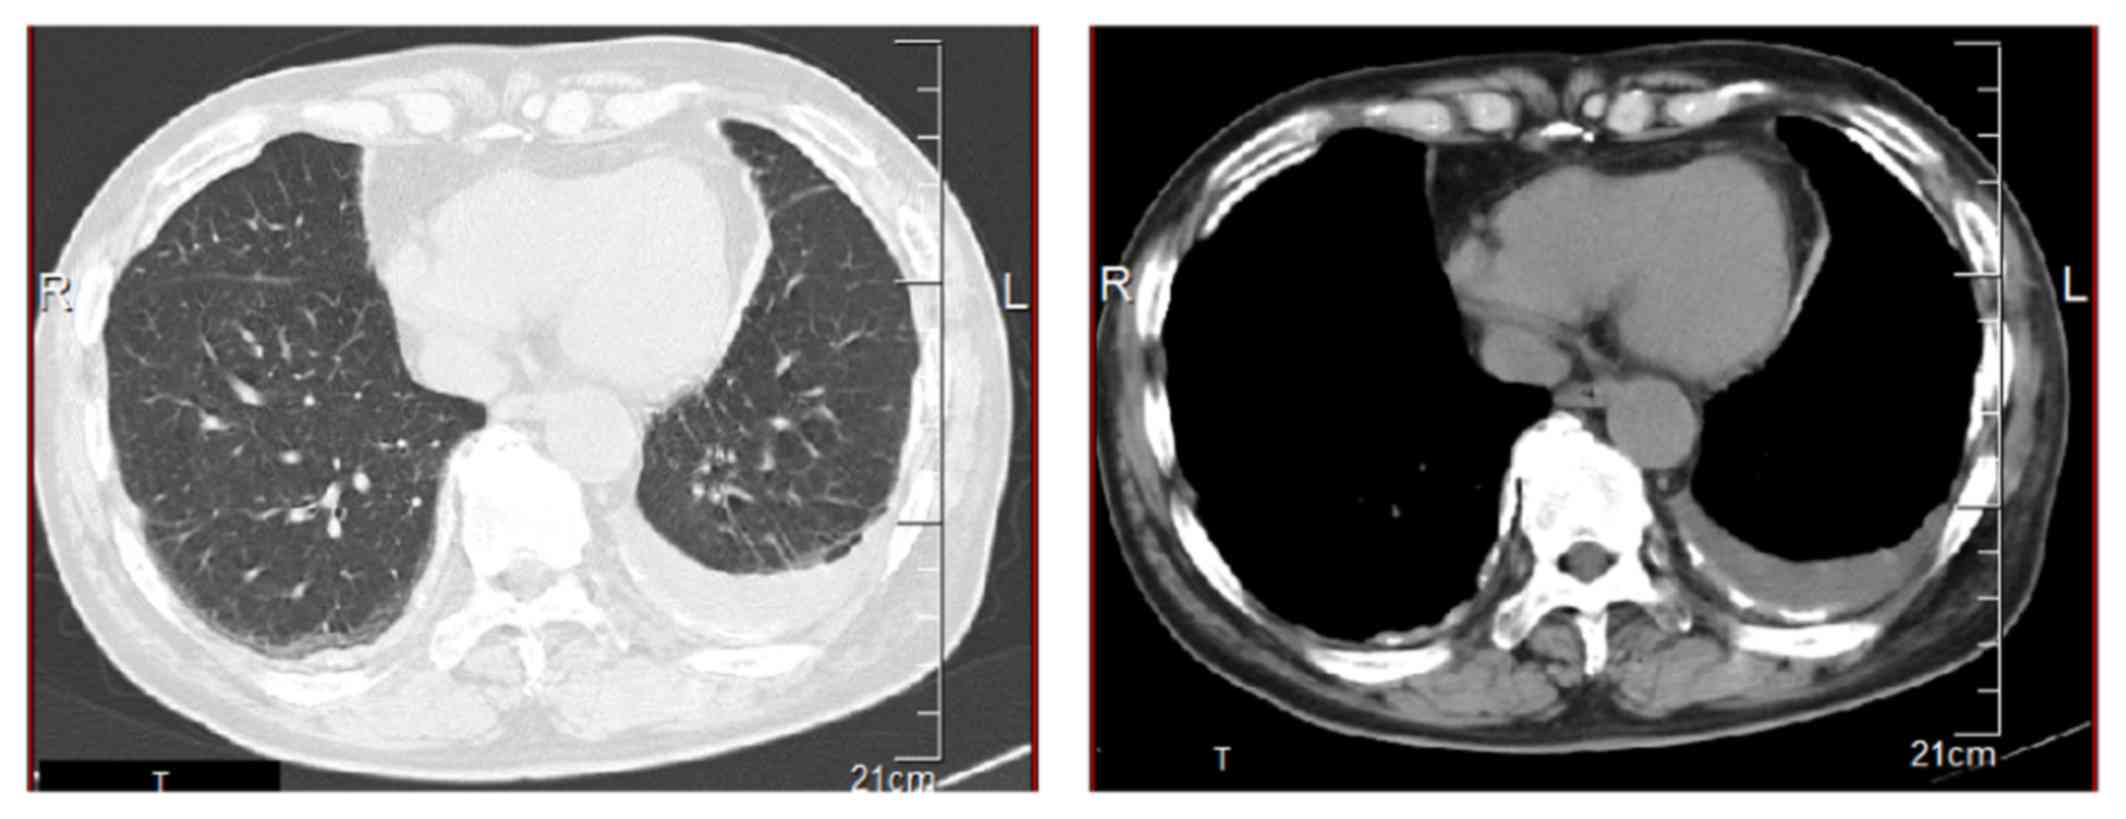

The findings of ct scan are similar to those of chest x ray but are seen better and in more detail.

The radiographic findings of mesothelioma are nonspecific and are observed in other diseases, including metastatic carcinoma, lymphoma, and benign asbestos disease. This tumor, previously uncommon, is now observed with increasing frequency in developed countries (pathogenetic relationship with asbestos fibers inhalation is proved). Imaging plays an essential role in the diagnosis, staging, and clinical management of patients with mesothelioma. A diagnosis of mesothelioma is most often obtained with careful assessment of clinical and radiological findings in addition to a confirming tissue biopsy. Mpm presents with several ct features similar to more common pleural diseases such as metastatic pleural malignancy.the aim of this study is to differentiate malignant pleural mesothelioma from metastatic.

Some people with years of asbestos exposure never develop mesothelioma. Small malignant pleural effusions may not be observed on standard radiographs.generally, abnormal chest x rays are followed by a more advanced imaging test, such as a ct scan. But computed tomography (ct) is the imaging technique of choice. Tap on/off image to show/hide findings. Even after making an initial diagnosis of mesothelioma, doctors may use ct scans to continually monitor treatment effectiveness and the overall status of their patient's disease. mesothelioma x ray findings : The findings of ct scan are similar to those of chest x ray but are seen better and in more detail. People diagnosed with mesothelioma have aggressive cancer that is caused by asbestos exposure. Common and uncommon findings are described and 8 new cases are presented. Fibers and occurs primarily as a result of occupational exposure. mesothelioma is rare, and there are no recommended screening tests for this cancer in. Standard posteroanterior and lateral chest radiography remains the most important technique for initial diagnosis of pleural effusion. The two most common types of mesothelioma are pleural mesothelioma and peritoneal mesothelioma.

Positron emission tomography (pet) scan. findings that might 5 _____american cancer society cancer.org | 1.800.227.2345 suggest mesothelioma include an abnormal thickening of the pleura, calcium deposits. She has received two shorty award nominations of which she won one, as well as seven streamy award nominations. Less commonly the lining of the abdomen and rarely the sac surrounding the heart, or the sac surrounding the testis may be affected. The most common anatomical site for mesothelioma is the pleura (the outer lining of the lungs and internal chest wall), but it can. Small malignant pleural effusions may not be observed on standard radiographs.generally, abnormal chest x rays are followed by a more advanced imaging test, such as a ct scan. Ct scanning provides more and better information than plain radiography with regard to tumor characteristic and extent. mesothelioma (or, more precisely, malignant mesothelioma) is a rare form of cancer that develops from cells of the mesothelium, the protective lining that covers many of the internal organs of the body. A clinical history of asbestos exposure and radiologic findings that are consistent with mesothelioma warrant inclusion of mesothelioma in the differential diagnosis, but it is important to stress that a diagnosis of mesothelioma cannot be made exclusively with imaging studies. The amount of fluid to be evident on a posteroanterior film is 200 ml, whereas costophrenic angle blunting can be appreciated on a lateral film when approximately 50 ml of fluid has accumulated. Repeated thoracenteses of bloody fluid were done. Like any other cancer issues. If you have been diagnosed with mesothelioma and experience any of these uncomfortable symptoms, you may have a pleural effusion.